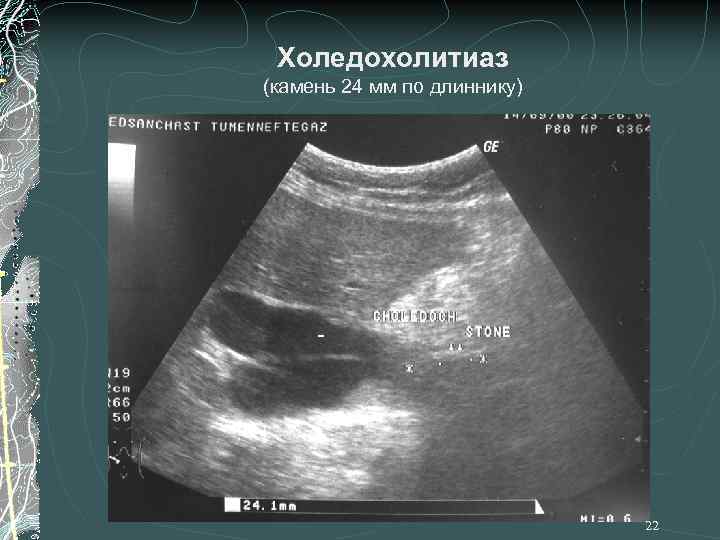

Холедохолитиаз (камень 24 мм по длиннику) 22